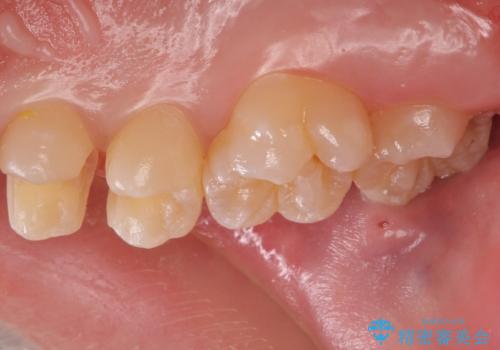

歯と歯の間の虫歯 セラミックインレーでの治療

- 検査の結果奥歯と奥歯の間に虫歯が確認されました。

虫歯を取り除いた後、セラミックインレーで修復していきます。

歯と歯の間は虫歯の好発部位になっています。

外からは確認しにくくても中で大きく虫歯が広がっていることはよくあります。